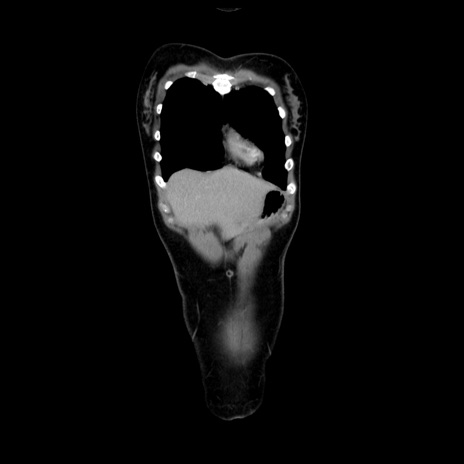

MRI(4日後)